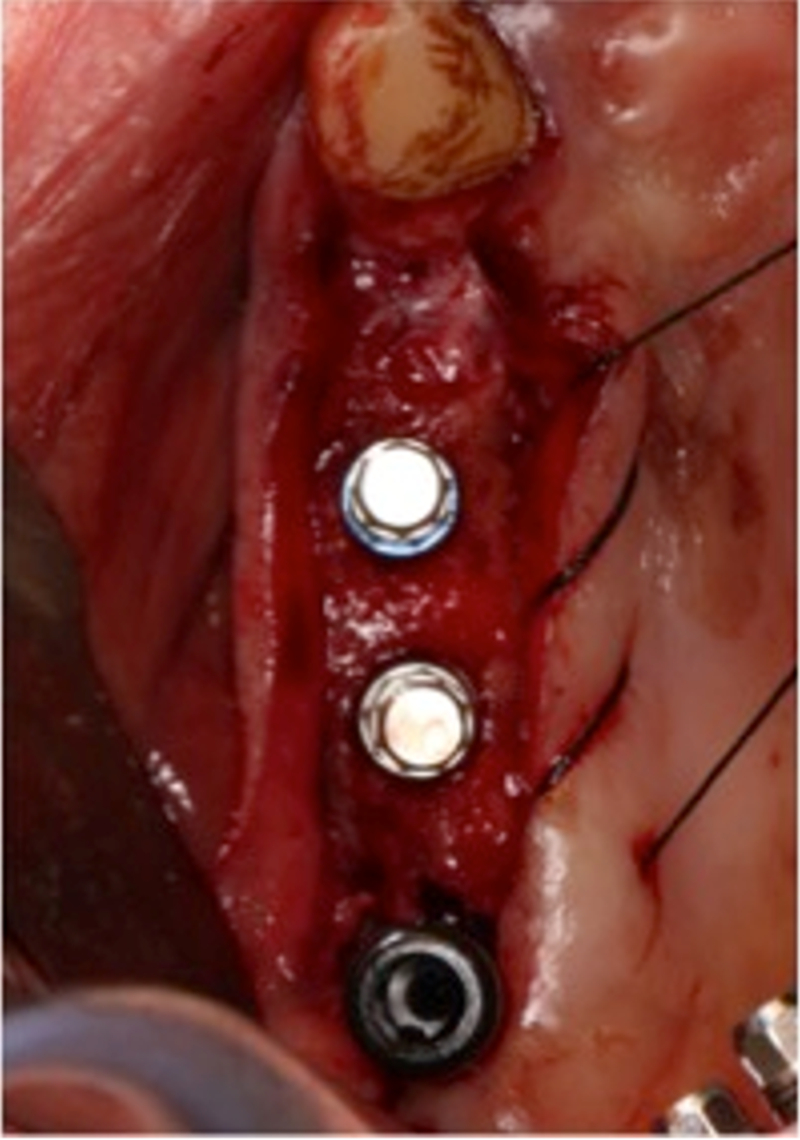

®完成3顆植體的植入,植體位點如術前方案設計,均在同軸線。

®進行縫合

®多顆植體位點及角度的精確性,確保后期修復方案順利完成,也使患者能在使用過程中承受最佳的咬合力